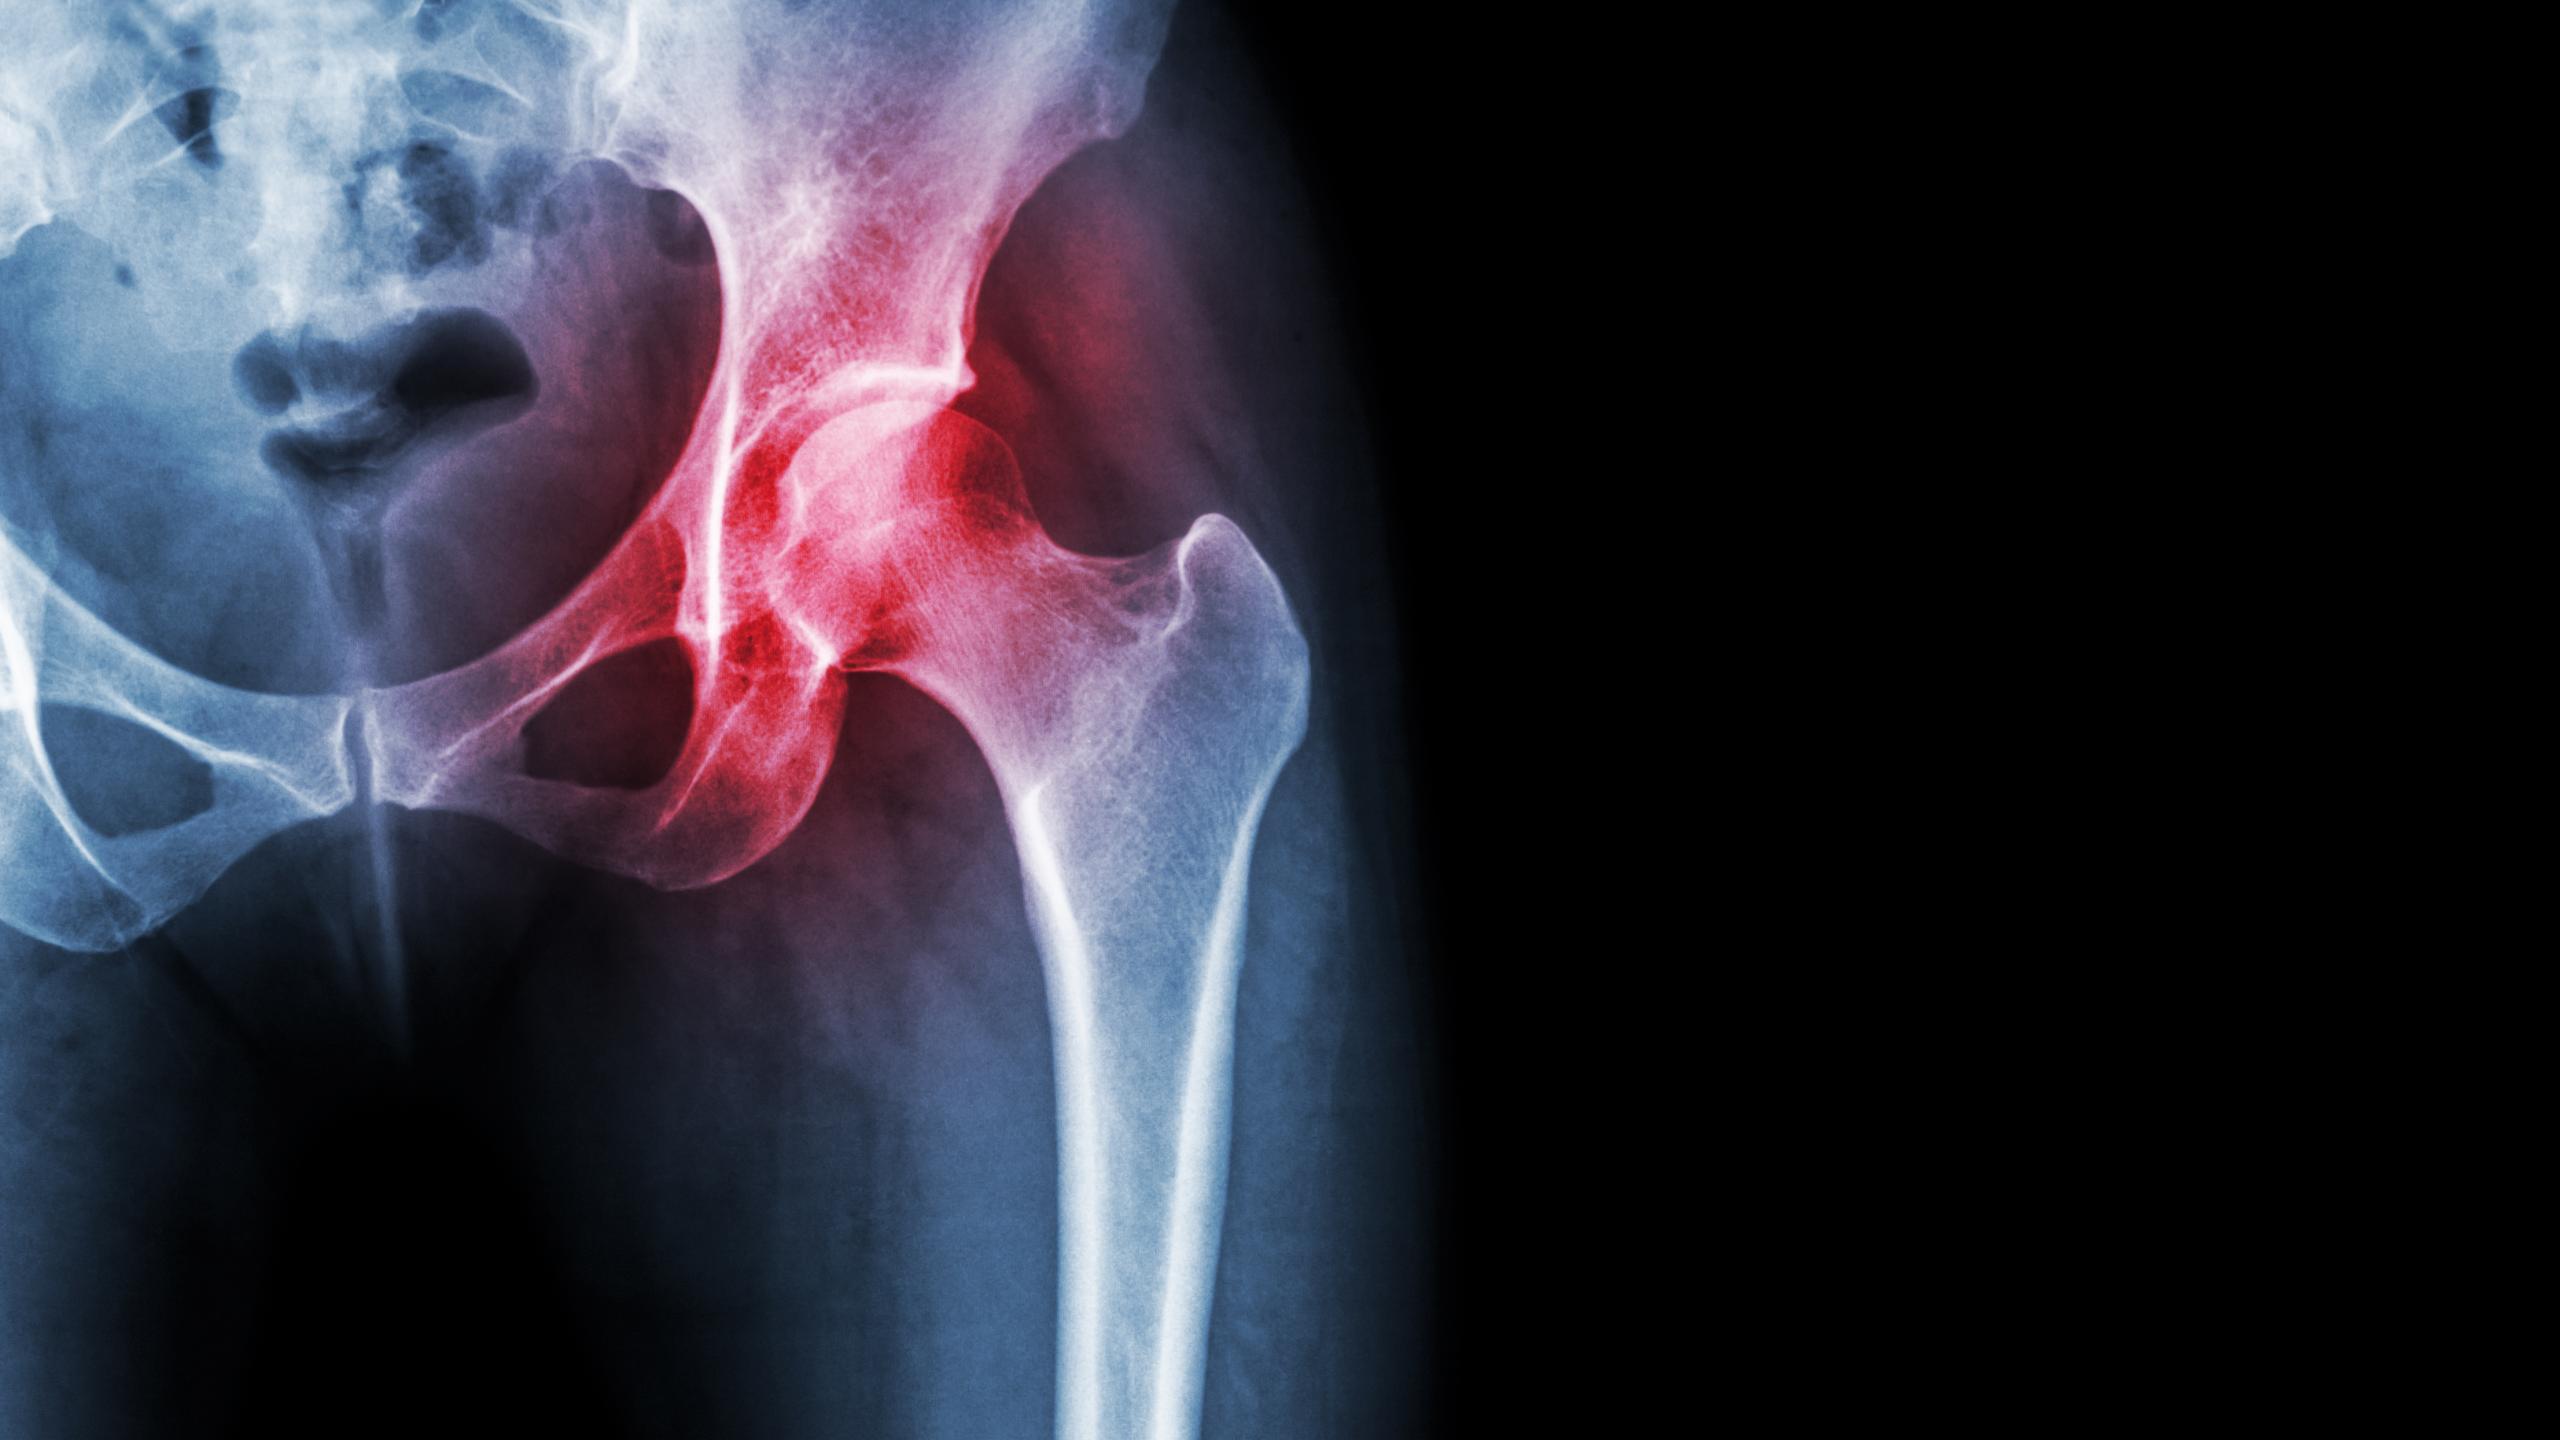

Ankylosing Spondylitis with SI Joint Fusion Ankylosing Spondylitis with SI Joint Fusion From ctisus.com

Ankylosing Spondylitis with SI Joint Fusion Source: ctisus.com